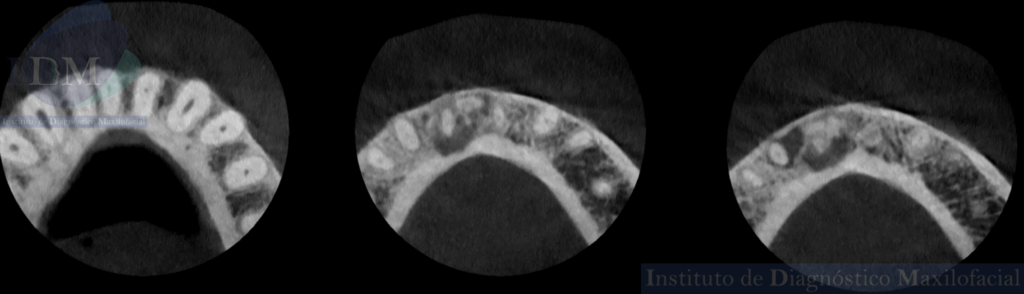

Así mismo en la tomografía volumétrica de haz cónico de campo reducido evidenciamos que dichas imágenes mixtas se encuentran comprometiendo zona a pical de la pieza 41 y 42 con un aumento de la densidad ósea adyacente. Siendo la imagen hipodensa a nivel a pical de la pieza 43 una probable lesión apical.

CORTES AXIALES